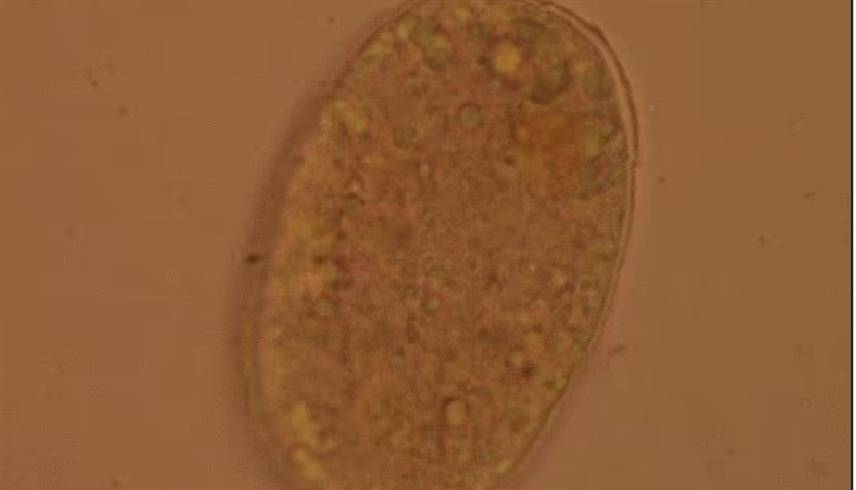

• أطباء يصورون ديداناً مصاصة للدماء في أمعاء امرأة